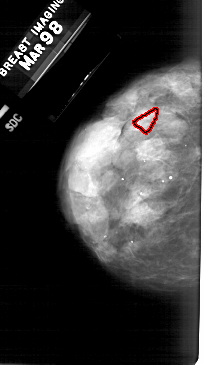

A_1484_1.LEFT_CC

LEFT_CC LINES 5101 PIXELS_PER_LINE 2851 BITS_PER_PIXEL 12 RESOLUTION 43.5 OVERLAY

FILE: A_1484_1.LEFT_CC.OVERLAY

TOTAL_ABNORMALITIES 1

ABNORMALITY 1

LESION_TYPE CALCIFICATION TYPE PLEOMORPHIC DISTRIBUTION LINEAR

ASSESSMENT 4

SUBTLETY 1

PATHOLOGY BENIGN

TOTAL_OUTLINES 1

BOUNDARY